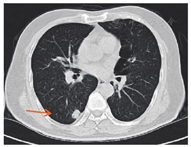

2012年7月起接受6次XELOX方案化疗,此后卡培他滨单药化疗1年;2013年7月影像学检查提示转移灶较前进展,肝脏出现新发转移灶;2013年9月16日针对肝转移瘤行射频消融术,2013年11月复查见肝Ⅷ段近膈顶处出现新病灶(图2)。2014年6月肺部CT未见明确转移灶,2014年11月右下肺考虑转移灶(图3)。2015年3月肺转移瘤较前进展,2015年3月起接受6个疗程FOLFIRI方案化疗(伊立替康150 mg/m2,ivgtt+氟尿嘧啶340 mg/m2,iv bolus+氟尿嘧啶2.2 g/m2,civ+亚叶酸钙330 mg/m2,ivgtt),2015年9月肝肺转移瘤均较前进展,2016年1月21日行肝转移瘤切除术,2016年2月胸部CT提示肺转移瘤进展,患者拒绝肺转移瘤介入治疗,2016年3月和4月行树突状细胞治疗。2017年3月肺CT:肺转移瘤增大,肝脏MRI肝Ⅷ段肿瘤存活(图4A),Ⅵ段新发转移癌(图4B)。2017年3月22日继续行FOLFIRI方案化疗,2017年4月—10月行10次西妥昔单抗+FOLFIRI方案化疗(伊立替康162 mg/m2,ivgtt+氟尿嘧啶365 mg/m2,iv bolus+氟尿嘧啶1.7 g/m2,civ+亚叶酸钙365 mg/m2,ivgtt+西妥昔单抗700 mg,ivgtt),2017年11月—2018年1月行5次西妥昔单抗单药(700 mg, ivgtt)靶向治疗,随访至2018年1月28日,生存时间超过94个月。